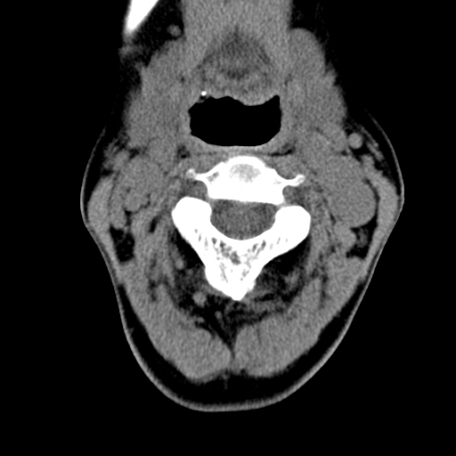

标题: CT24010:患者女56岁双侧甲状腺摘除术后一月复查,患者现感 [打印本页]

标题: CT24010:患者女56岁双侧甲状腺摘除术后一月复查,患者现感

甲状腺术后复发,现在甲状腺区域仍有密度不均匀之软组织密度影。

甲状腺区域密度不均匀密度影,应该是术后改变,要鉴别是否复发,建议增强检查。

“甲状腺摘除术后一月复查”,有病理吗?考虑术后复发,可能是恶性,颌下及左侧颈部淋巴结有肿大。

考虑术后复发,并颈部淋巴结肿大。请结合临床。

双侧甲状腺肿大,伴多发低密度灶(性质待定);建议行进一步检查。

双侧甲状腺肿大,周围结构不清,术后复发时间有点短,考虑出血并感染。